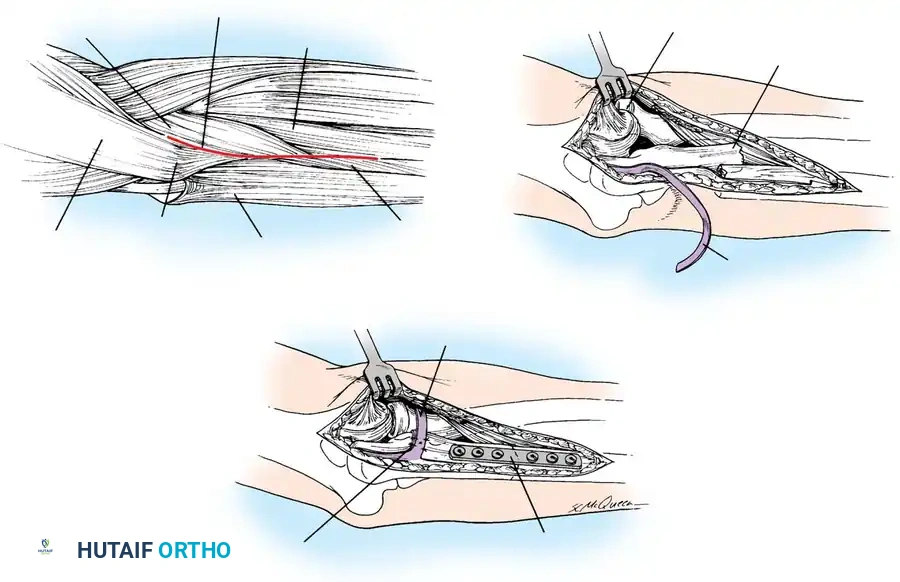

🔪 Surgical Technique: Excision and Triceps Advancement

- Fragment Removal: Carefully dissect the comminuted fragments from the triceps tendon, preserving as much tendon length as possible.

- Joint Debridement: Inspect the joint and remove all intra-articular debris.

- Bone Preparation: Smooth the remaining proximal end of the ulna. If the midportion of the olecranon is comminuted but the proximal tip is intact, the central comminuted segment can be excised (Barford technique). The osteotomies must be directed accurately along the radius of the trochlear curve to reconstitute a smoothly curved notch.

- Triceps Advancement: Drill two or three longitudinal holes through the remaining proximal ulna. Pass heavy non-absorbable sutures (e.g., #2 or #5 FiberWire) through the triceps tendon using a Krackow stitch, pass them through the drill holes, and tie them securely over the posterior ulnar cortex with the elbow in 30 degrees of flexion.

Fig. 54-57 Technique of excision of central one third of olecranon process (Barford, 1972). It is critical to err by making the radius of the notch too large, rather than too small.